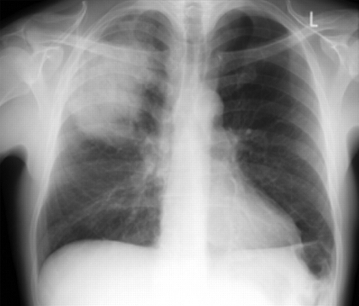

Nova sombra (consolidação) na radiografia torácica confirma o diagnóstico de PAC[1][63][65]

Reavalie o paciente se a radiografia torácica não mostrar consolidação.[1][Figure caption and citation for the preceding image starts]: Radiografia de tórax posteroanterior mostrando consolidação do lobo superior direito em um paciente com pneumonia adquirida na comunidadeDurrington HJ, et al. Recent changes in the management of community acquired pneumonia in adults. BMJ 2008;336:1429. [Citation ends].